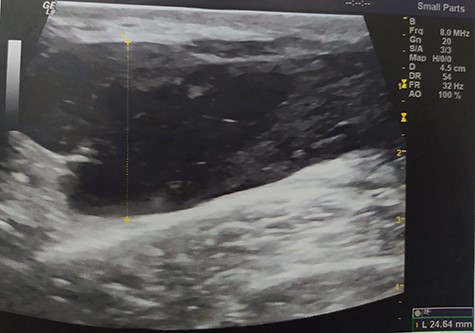

A 55-year-old Caucasian male proceeded to our institution complaining about irreducible swelling of the right iliac fossa and constant discomfort, over the course of a year. His medical history revealed that he slapped against a blunt surface of a furniture a year ago and injured his right groin and pelvis. Due to the accident and the subsequent painful swelling, the patient underwent immediately a pelvic ultrasound the detected an acute hematoma with a diameter of 52 mm into the fatty tissue of the right pelvic fossa (Fig. 1). Ten months after the accident, due to the irreducible swelling, the patient underwent another ultrasound revealing a nonorganized hematoma with thrombotic features (sized as 25 × 60 × 58 mm) (Fig. 2).

Pelvic ultrasound indicating an acute/nonorganized hematoma into the fatty tissue of the right iliac fossa, with thrombotic features.